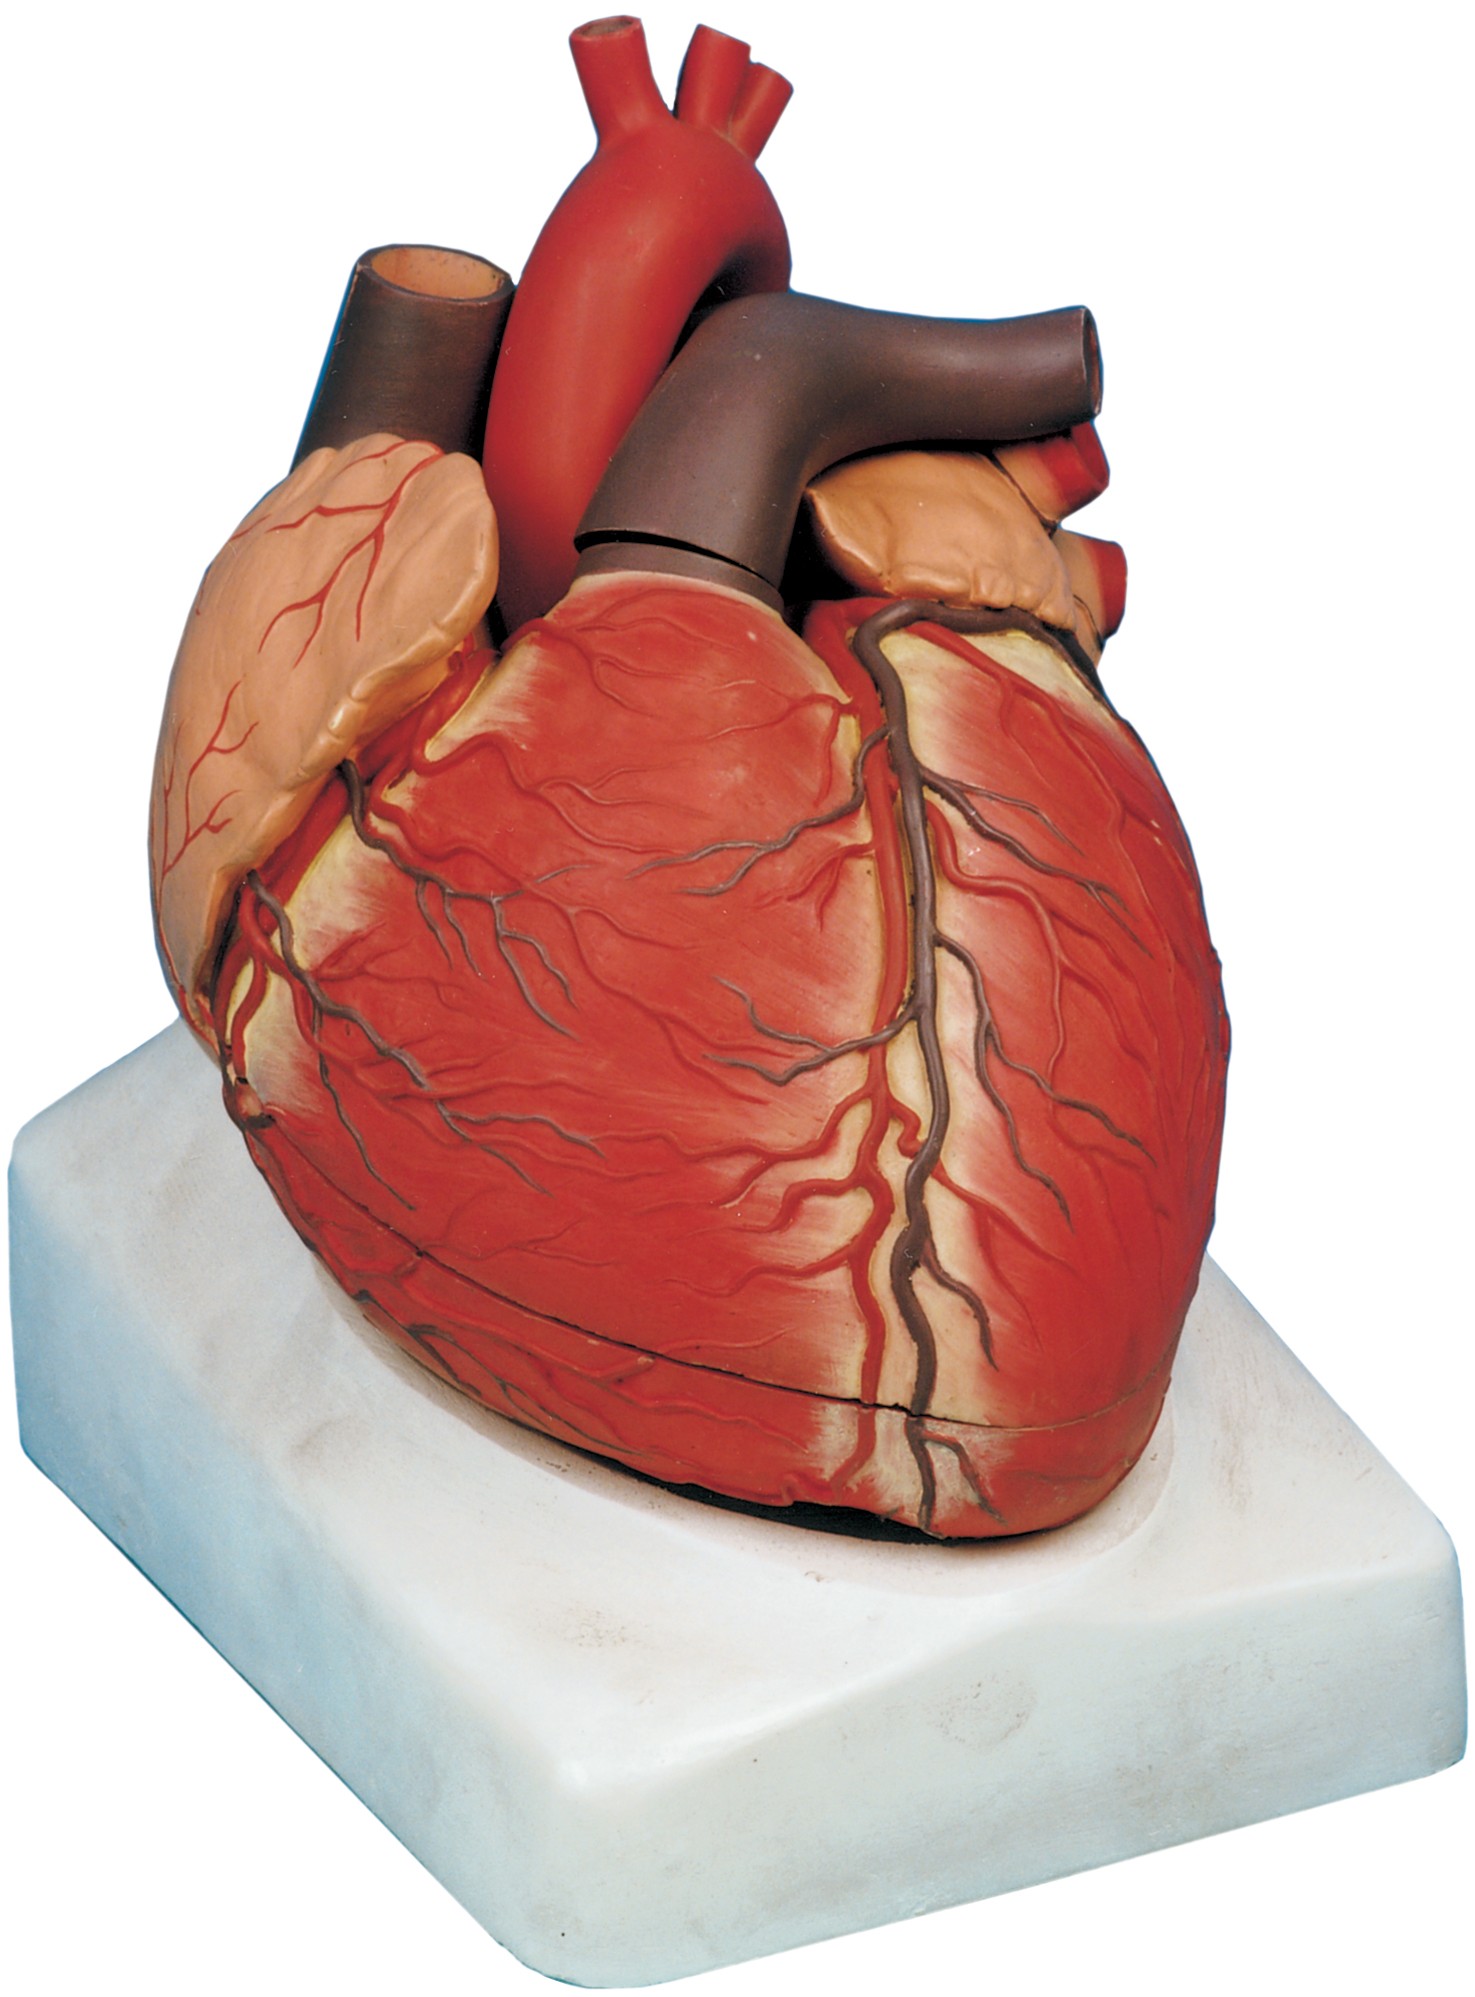

مولاژ کلمه ای فرانسوی به معنای قالب است. آناتومی بدن انسان با تجهیزاتی مانند مولاژهای پزشکی یا کالبدشناسی که نمونه هایی تخصصی و شبیه به اندام های بدن انسان هستند، به دانش آموزان و دانشجویان آموزش داده می شود. استفاده از مولاژ در روند یادگیری و آموزش تاثیر به سزایی داشته و تمامی اندام ها را با تمامی جزئیات و با کیفیت بالا می توان مشاهده و بررسی کرد. مولاژها عموما از جنس PVC نشکن، لاستیک یا فوم ساخته شده و دارای رنگ طبیعی و قابل شست و شو هستند. برخی از انواع مولاژها مناسب برای آموزش مراقبت های پزشکی و پرستاری است و امکان تمرین بانداژ، تزریق، CPR، جراحی و... وجود دارد. مولاژها معمولا هر کدام عضوی از بدن را نمایش می دهند و قابلیت تفکیک و مشاهده همه بخش های آن وجود دارد.

مولاژها معمولا با توجه به نوع اعضا و یا دستگاه های بدن در اندازه طبیعی، کوچکتر و یا چندین برابر بزرگتر ساخته می شوند تا امکان مشاهده دقیق اجزای آن ها فراهم شود. برخی مولاژها از چندین قطعه ساخته شده اند که قابلیت تفکیک دارند. علاوه بر نمایش ساختار و نحوه عملکرد اعضای بدن، ماهیچه ها و عضلات بدن را نیز می توان به کمک مولاژها مشاهده کرد.

مولاژها ابزاری تخصصی برای آموزش دانشجویان پزشکی، دندان پزشکی، پرستاری و مامایی است. همچنین در مدارس و سایر مراکز آموزشی میتوان از انواع مولاژها برای بهبود یادگیری و آموزش بهره برد. در کلینیک های زنان و زایمان، دندان پزشکی، سالن های تشریح، بیمارستان ها و آزمایشگاه ها نیز مولاژهای مراحل حاملگی، انواع دندان و بیماری های آن کاربرد دارند.